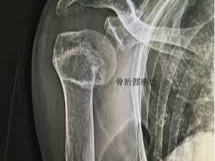

상완골 골절 치료기간 과 깁스, 슬링, 고정 기간

많은 분들이 상완골 골절 치료기간을 말할 때 “깁스를 몇 주 하느냐”를 궁금해하지만, 실제 어깨뼈 골절 치료방법은 다리처럼 완전 석고고정만 하는 경우보다 슬링이나 보조기로 지지하는 방식이 더 흔합니다.

근위 상완골 골절 환자 안내자료들을 보면 슬링은 대개 3주에서 6주 정도 사용하는 것으로 설명하고, 견갑골 골절은 초기에 3주 전후 슬링을 사용한 뒤 점진적으로 움직임을 늘리는 방식이 많습니다. 물론 고정 기간이 길수록 뼈가 안전하게 붙을 것 같지만, 어깨는 너무 오래 고정하면 강직이 심해져 이후 재활이 더 어려워질 수 있습니다. 그래서 정형외과에서는 통증과 안정성을 보면서 손가락, 손목, 팔꿈치 운동은 비교적 일찍 시작하고, 어깨도 수동운동이나 보조운동을 단계적으로 도입하는 경우가 많습니다.